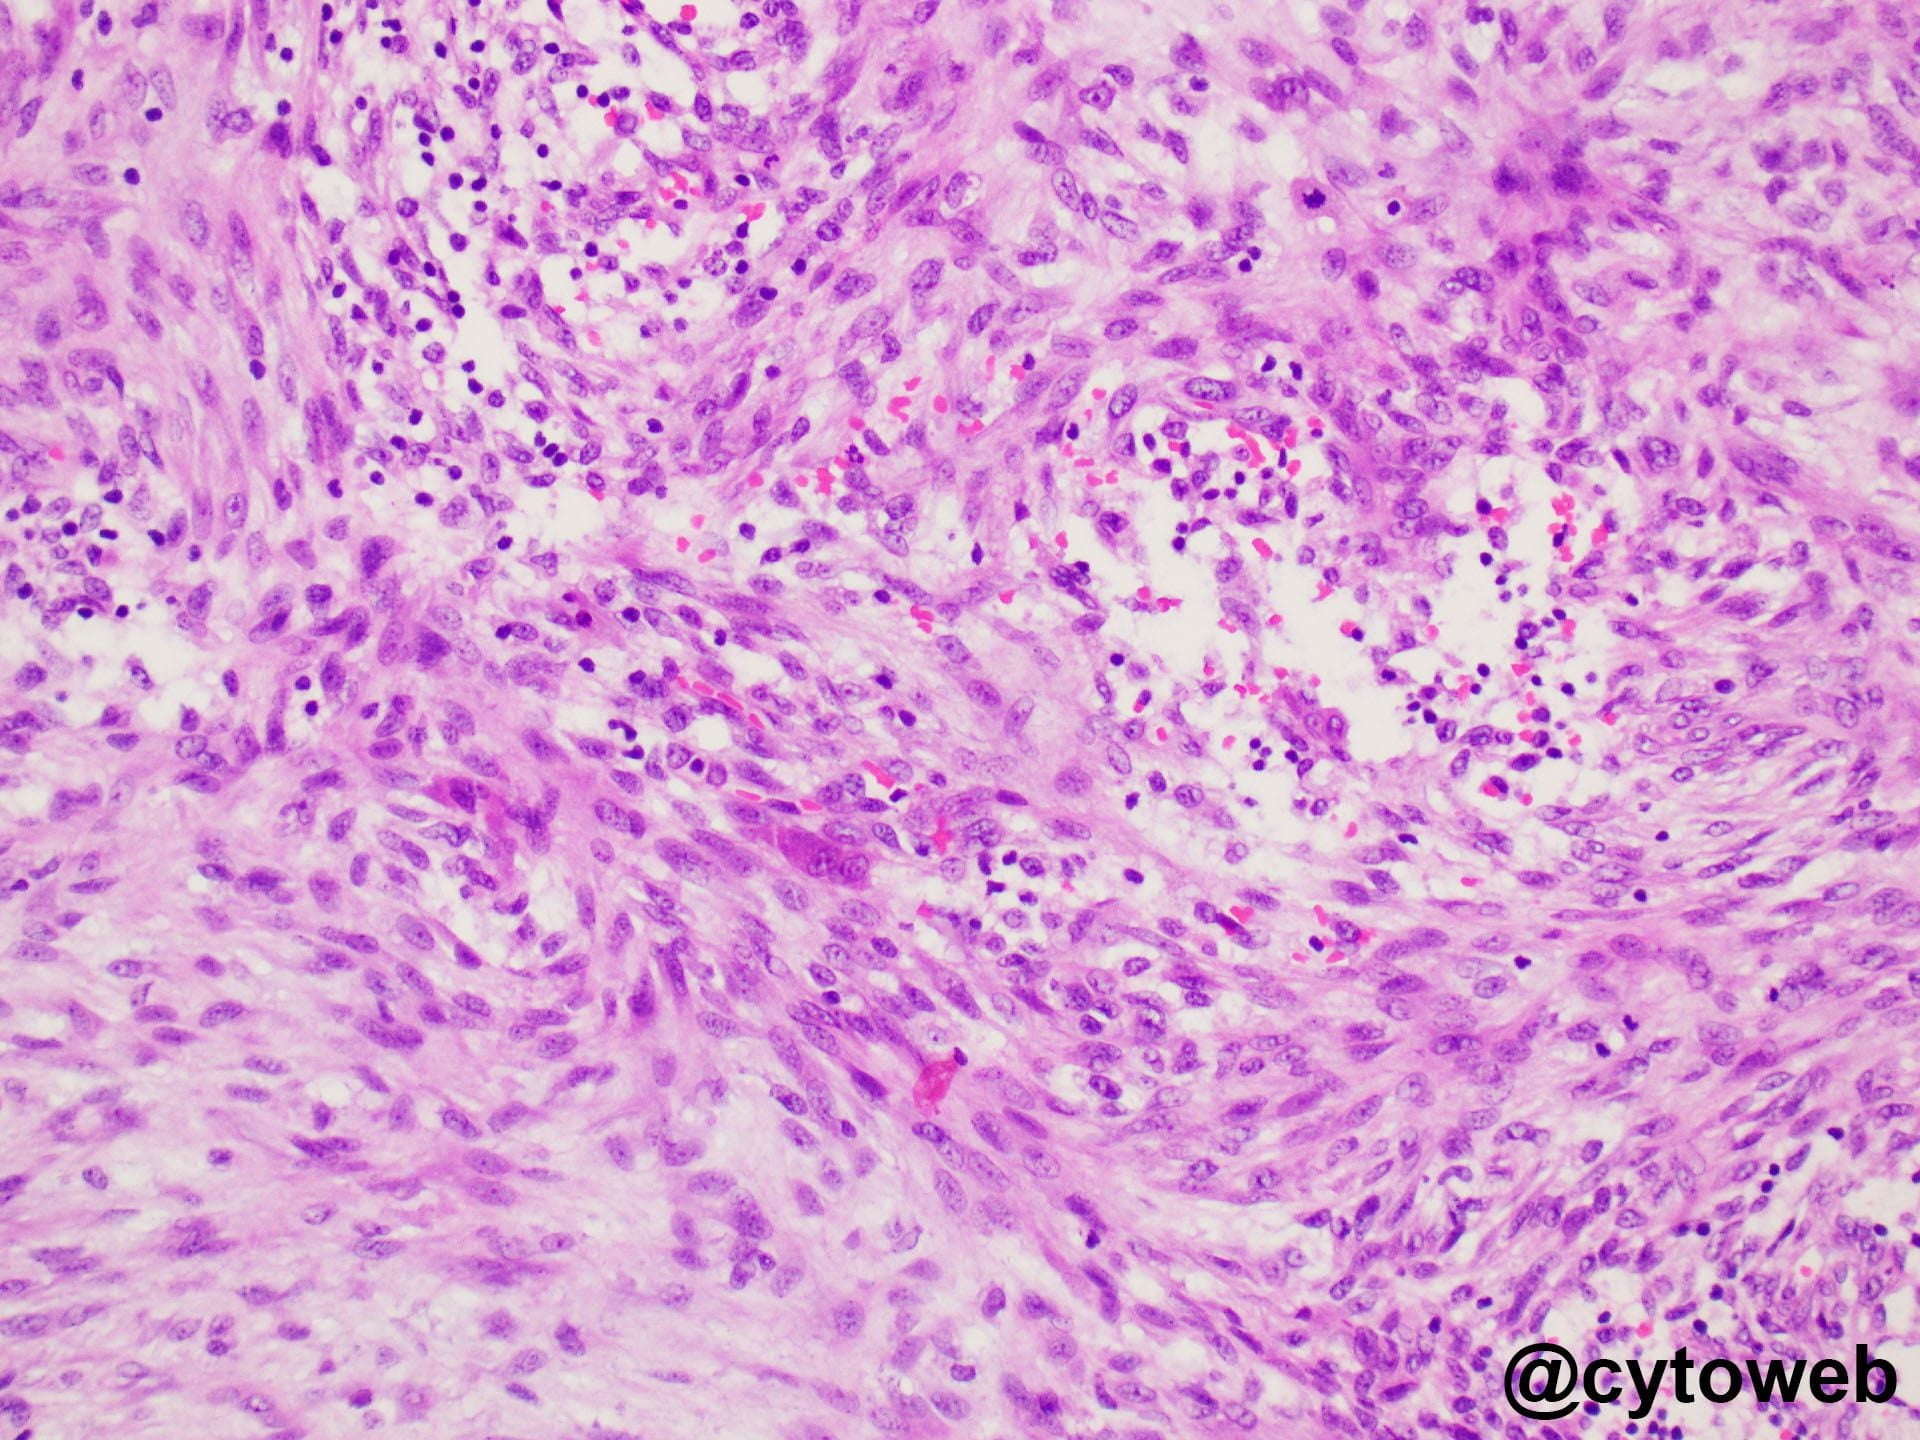

- Nodular fasciitis

- Spindle to stellate cells occurring in clusters and as singly dispersed cells; can be associated with mxyoid stroma

- Cells have abundant cytoplasm and tapering cytoplasmic processes

- Inflammatory cells often seen

- Can have relatively frequent mitoses

- If cell block is available – lesional cells are positive for SMA